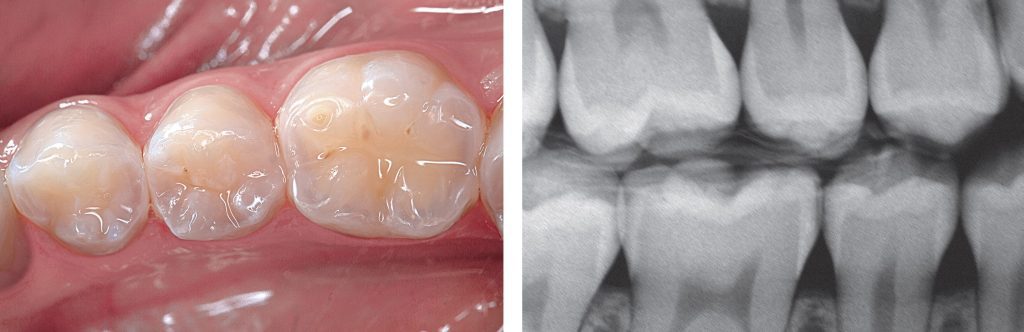

Hình 12. Sâu răng phía xa R35 được phát hiện khi chụp X quang và khám lâm sàng.

Hình 22. Hoàn tất phục hồi composite và kiểm tra X quang cho thấy sự tích hợp hài hòa giữa composite và cấu trúc răng ở vùng kẽ răng.